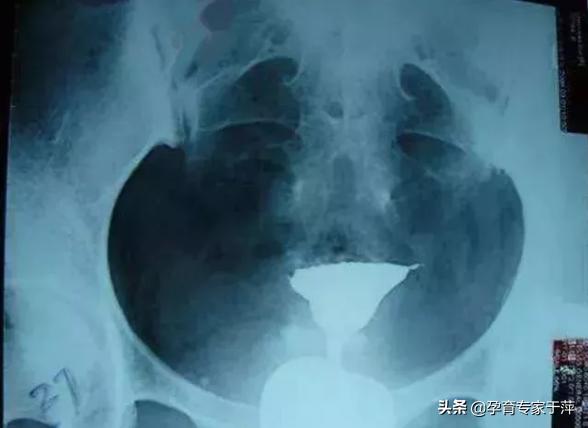

1、输卵管通畅

可以看到一侧或双侧输卵管伞端有造影剂溢出,盆腔有造影剂涂抹。